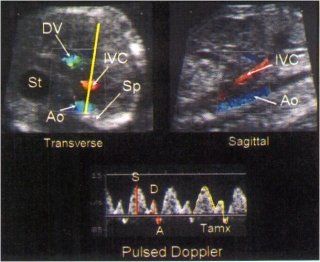

There are two approaches which can be used to image the inferior vena cava with color Doppler ultrasound to obtain the pulsed Doppler waveform. The first requires the examiner to direct the ultrasound beam transversely through the fetal abdomen at the level of the stomach. After activating the color Doppler using a low velocity setting (<0.24 m/s), three vessels can be imaged in cross-section: the abdominal aorta, the inferior vena, and the ductus venosus

In 1990 Reed and co-workers published results from a study of 16 normal fetuses in which they measured the peak velocity and the Tamx of the S, D, and A waves

Following the report by Rizzo’s group, Hecher group in 1994 reported results from 127 normal fetuses in which the peak velocities of the S, D, and A waves were measured. The computed indices included the Tamx for the entire waveform (S+D+A), the PVIV and the PIV 24. Hecher’s study found that, as the fetus grew, there was an increase in peak velocity of the S and D waveforms, as well as the amount of blood returning to the right atrium, as represented by an increase in the Tamx of the waveform. The decrease in the PVIV and the PIV were the result of a decrease in the peak velocity of the A wave. The decrease in the velocity of the A wave most likely was the result of a decrease in right ventricular afterload and/or an increase in ventricular compliance. Unlike Rizzo’s group, who reported reverse flow of the A wave for all normal fetuses, Hecher and colleagues reported that reverse flow became less frequent as gestational age increased 8,24. Review of Hecher’s graphical data suggested that less than 10% of fetuses had reverse flow of the A wave after 31 weeks of gestation24. The absence of reverse flow of the A wave in all normal fetuses was suggested by Reed and co-workers in their small series, and, more recently in a study by Gudmundsson and colleagues who noted that 37% of normal fetuses had no reversal of the A wave 7,24. After excluding fetuses without reversal of the A wave, Gudmundsson’s group demonstrated a decrease in the percentage of reversal of A wave flow as gestational age increased 29. As the result of this observation, the PIV and PVIV advocated by Hecher and colleagues, may be the most appropriate non-angle dependent method for evaluating venous waveforms since these equations allow for the measurement of forward, reverse, or absent flow during atrial systole 24.